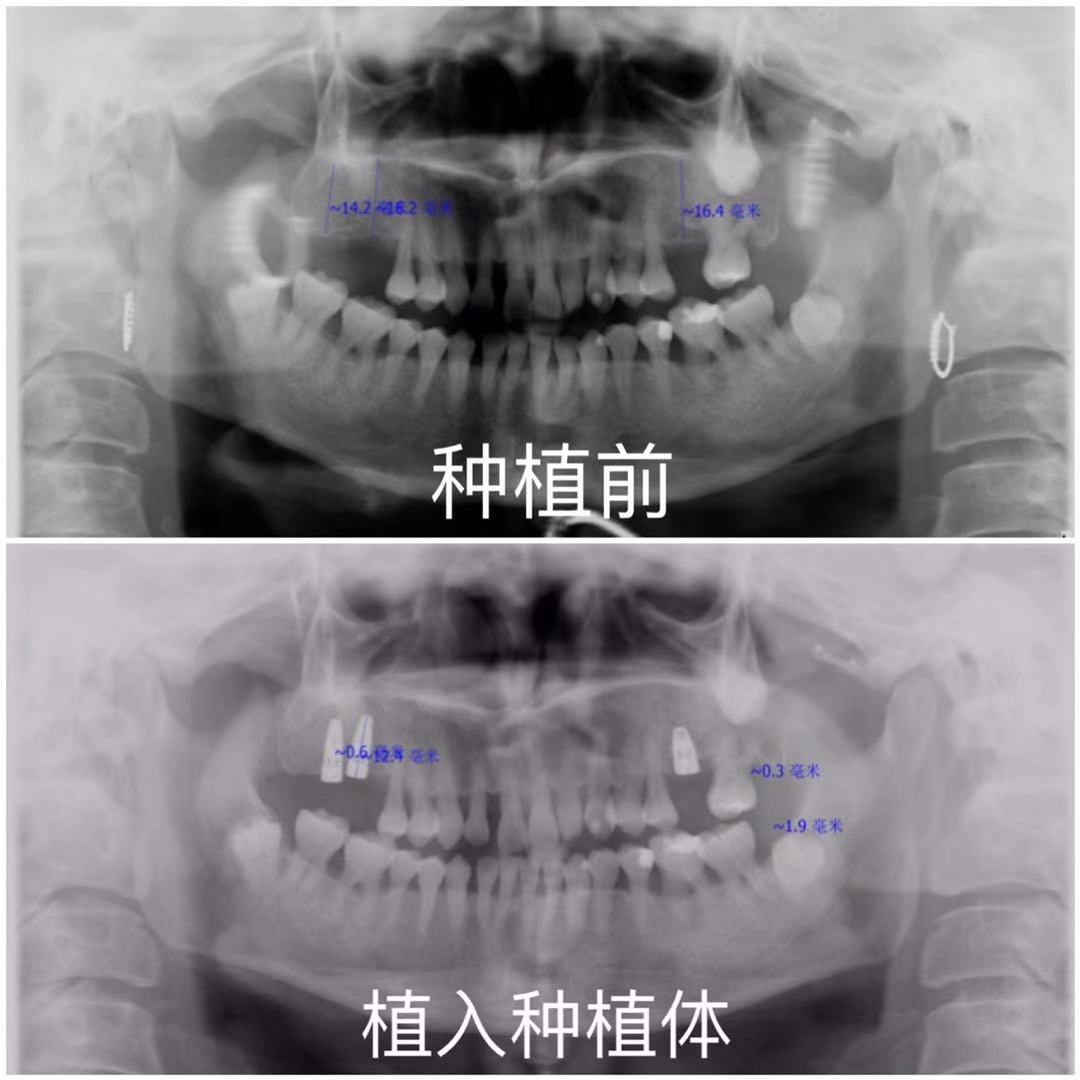

种植前后对比

几年前上颌后牙在外院进行拔除,后因为咀嚼受到影响来院做种植牙

诊断:缺失,缺牙区牙槽嵴中度萎缩,无骨尖、软组织增生。冷(-),探(-),叩(-),松(-)。牙周情况不好,关节未见明显异常

植体个数:3颗;

植体种类:NOBELREPLACE种植体;

右上6,7型号:5.0*11.5 mm,左上6,型号:5.0*8mm